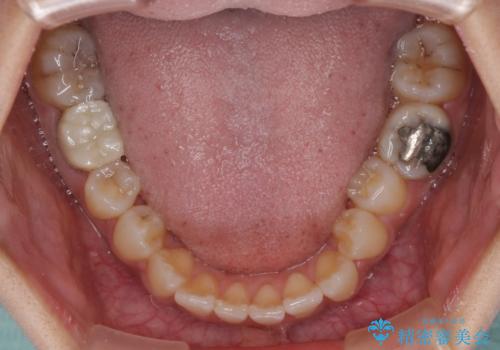

- 上の歯の歯並びを気にして来院された患者様です。

上顎骨の横幅が狭く、歯列が混み合っていたため、急速拡大装置により側方拡大し、咬み合わせと歯列を改善することとしました。

下顎は部分的に咬み合わせに問題があったため、部分的な装置を付けることとしました。